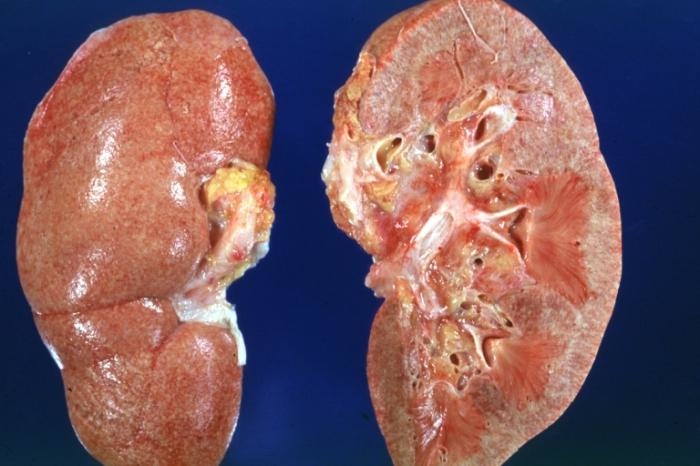

Пиелонефрит представляет собой воспалительное заболевание, вызванное бактериальной инфекцией, которое затрагивает как почечную ткань, так и лоханку. Это заболевание имеет неспецифический характер, что означает, что его могут вызывать различные бактерии, такие как кишечная палочка, энтерококк, протей, синегнойная палочка, стафилококк, стрептококк и клебсиелла. Эти факторы играют важную роль в выборе методов лечения. Инфекция может проникать в паренхиму почки через сосуды или по мочеточникам из мочевого пузыря.

Важно помнить о возможных осложнениях, так как они могут привести к почечному отеку, образованию абсцесса или почечной недостаточности.